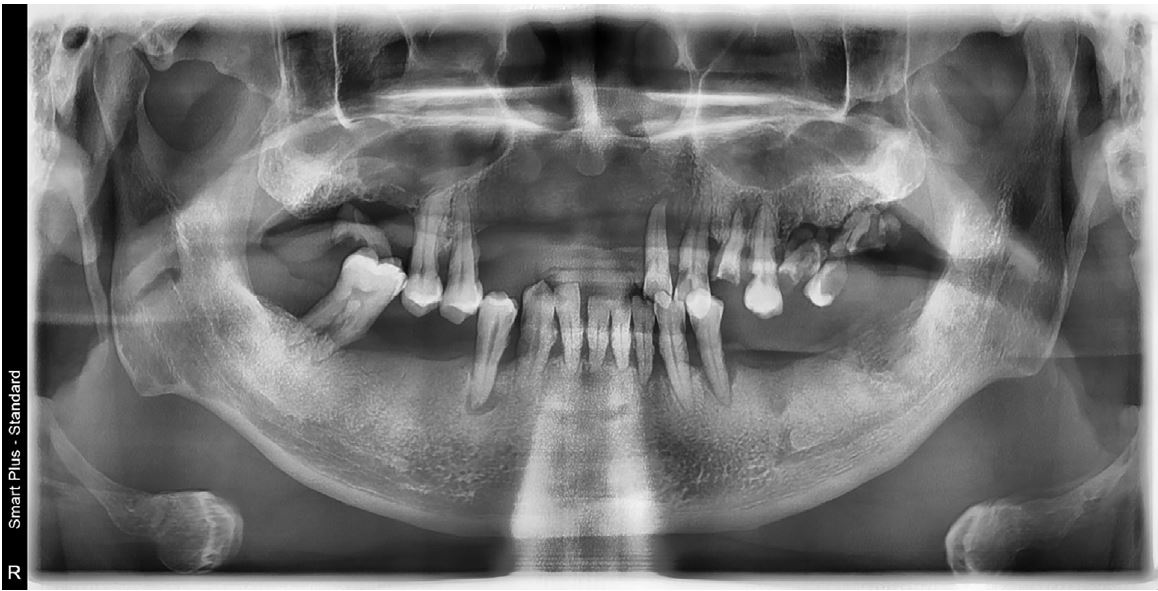

A 51-year-old male patient with no history of any serious disease visited a dentist with chief complaints of full-mouth implant treatment. Based on the initial clinical and radiographic examinations, the patient had severe periodontitis and was found to have multiple teeth with grade 3 mobility and heavy calculus deposition. In addition, many residual roots and teeth with advanced dental caries were observed (Fig. 1). A vertical stop was made in the left maxillary canine and left mandibular first premolar, and mastication was performed consistently on these teeth. No centric occlusion-centric relation (CO-CR) discrepancy was observed. The vertical dimension maintained by the left maxillary canine and left mandibular first premolar was judged to be satisfactory during the initial examination. In addition, full mouth scanning with an intraoral scanner (Trios 3; 3Shape, Copenhagen, Denmark) was conducted to use it as a reference point for the vertical dimension of the provisional prosthesis in future (Fig. 2).